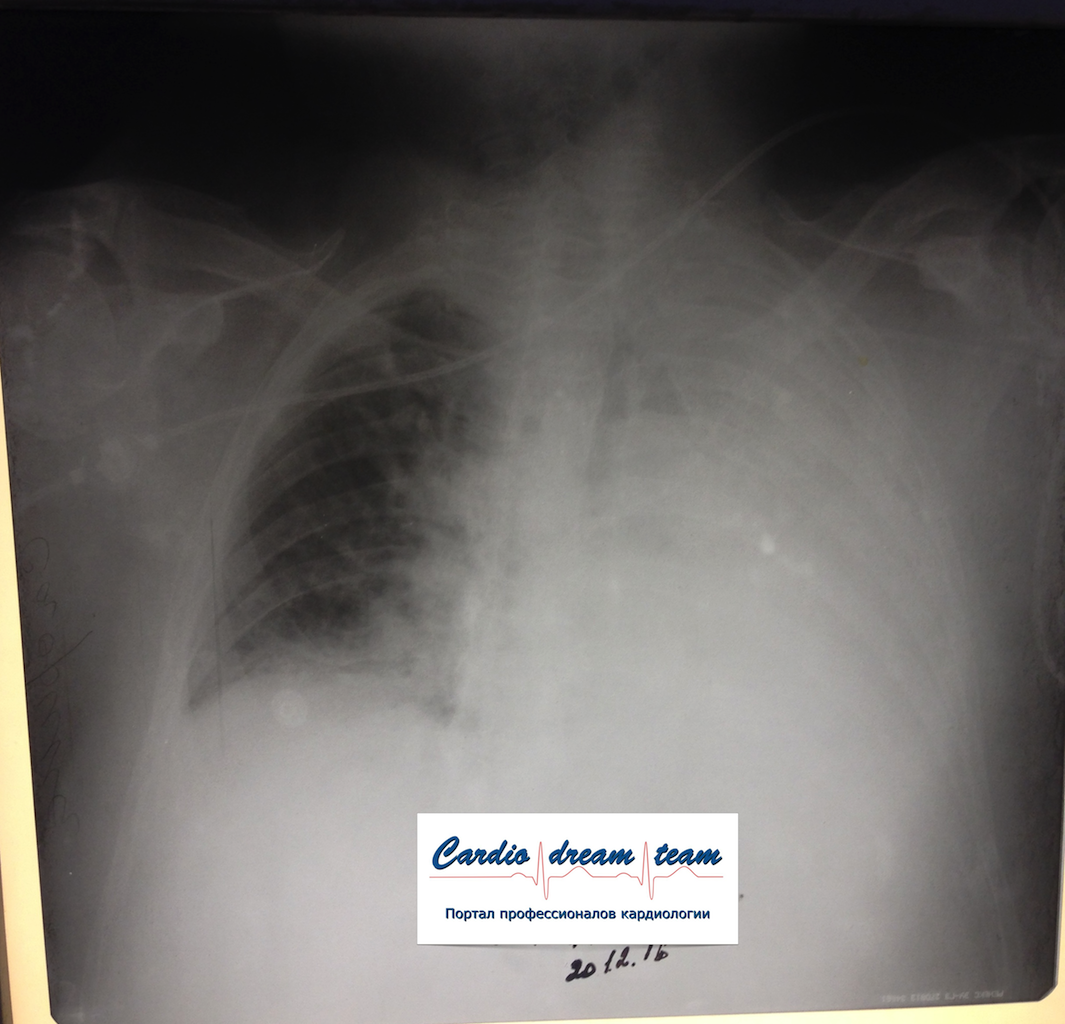

Ателектаз слева. Центральный рак.

Обсуждалось в Госпитале Ослабленных Сердец